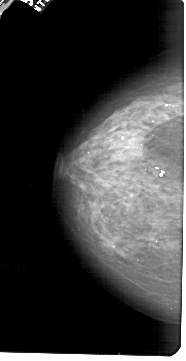

A_1488_1.RIGHT_MLO

RIGHT_MLO LINES 5491 PIXELS_PER_LINE 3016 BITS_PER_PIXEL 12 RESOLUTION 43.5 NON_OVERLAY